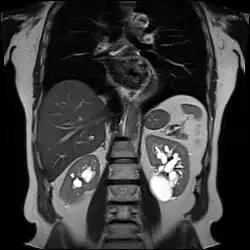

Renal ultrasonography of a simple renal cyst with posterior enhancement. -

Advanced polycystic kidney disease with multiple cysts.[13] -